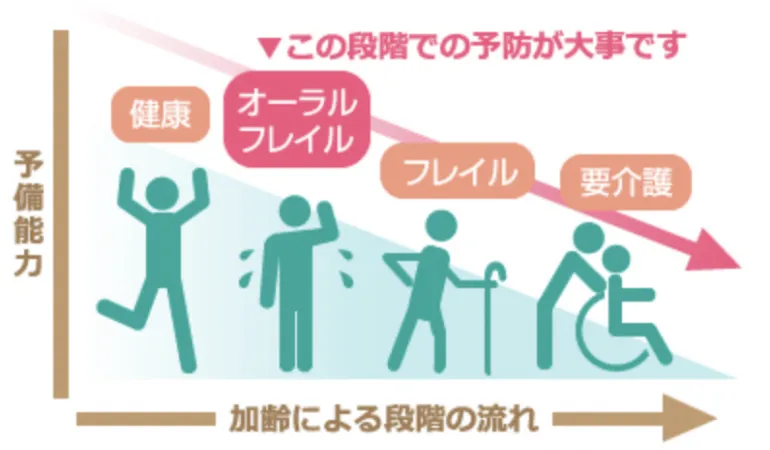

お口の機能が本格的に衰える前に

予防できることがあります

実は加齢による体の機能の減退は口の機能の衰えに密接に関係しています。

口の機能の衰えを放置しておくと、飲食物の咀嚼や飲み込みが困難になる障害や要介護状態につながります。本格的に悪くなる前の「オーラルフレイル」の段階での予防が大切になります。

失った歯を補う治療に入れ歯やブリッジがありますが、残っている歯に負担がかかる傾向にあり、長期的に歯を消耗させていくことにも繋がります。

失った歯の部分にインプラント治療による歯を復活させることで、残っている他の歯を守り、長期的に噛み合わせもしっかり構築します。

「オーラルフレイル」の段階でしっかり予防することで、健康寿命が延びると言われています。現在や将来の歯についての悩みや不安、インプラント治療のこと、何でも遠慮なく私たちにご相談ください。